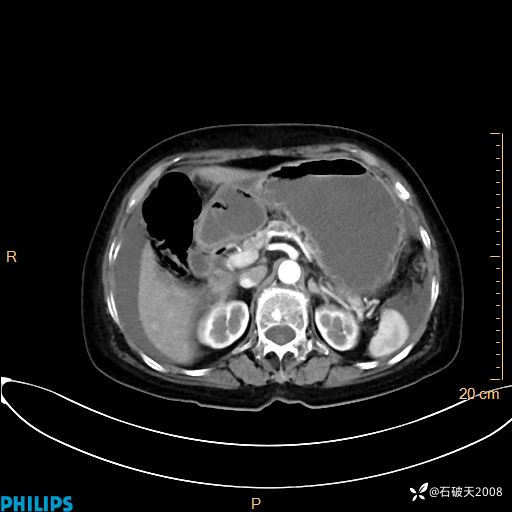

MIP